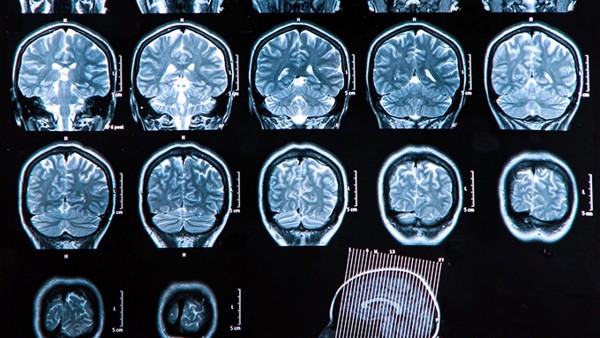

脑梗塞的病因主要与脑梗塞的发病机制有关,其中临床脑梗塞主要包括动脉粥样硬化性脑梗塞、脑栓塞、分水岭脑梗塞和腔隙性脑梗塞。其中动脉粥样硬化性脑梗死是由动脉粥样硬化引起的血管狭窄,在血管狭窄的基础上可能发生血管进一步闭塞。因此,对于动脉粥样硬化脑梗塞的患者,建议平时口服抗动脉粥样硬化药物,积极治疗动脉粥样硬化的病因。

患者在脑梗塞急性期间可能会导致血压升高,部分患者的血压可能正常。因为脑梗塞发生时,患者的脑供血突然减少,反弹性有可能导致血压上升。由于人体大脑具有调节功能,可能会导致高血压,但部分患者的血压仍然正常。引起脑梗塞的主要危险因素包括高血压、糖尿病、高脂血症、高同型半胱氨酸血症等其他疾病。

上述疾病都是引起脑梗塞的危险因素,患者脑动脉硬化程度恶化,容易引起脑血栓。另外房颤、心脏瓣膜疾病导致附壁血栓脱落,也是脑梗发生的主要原因。因此,当身体明显不适时,建议患者及时到正规医院就诊,以免加重症状,错过治疗时机。